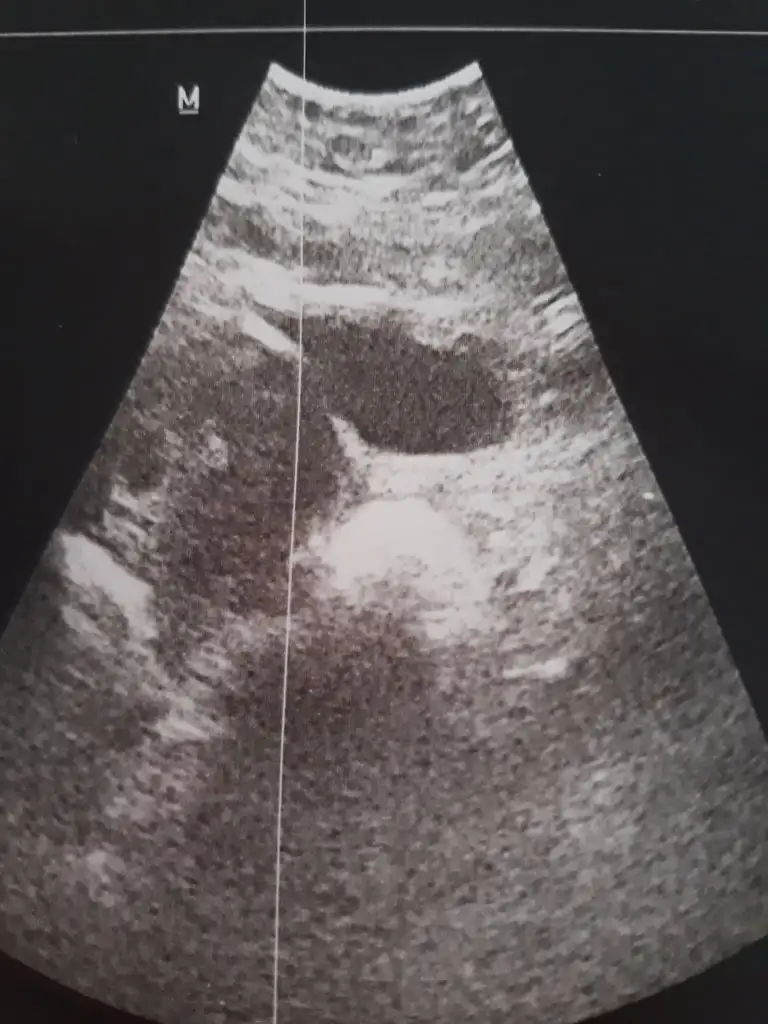

İlk hamileliğim ve çok beklediğim bebeğimin cinsiyetini çok merak ediyorum kese konumuna göre bebeğin cinsiyetini tahmin edecek arkadaşlar tahminlerinize ihtiyacım var şimdiden çok teşekkür ediyorum 12 haftalık

Anladım nasip o zaman ilk gebelik de ortadaydı kese bunda soldaSol erkek sağ kız olur derler ne kadar doğru bilmiyorum tabi o yüzden sizinki erkek gibi. Benim sagdaydi yarın net cinsiyeti ogrenicem bakalım uyuyor mu doğruluk payı var diyebilir miyim

Sol erkek sağ kız karında usgAnladım nasip o zaman ilk gebelik de ortadaydı kese bunda solda